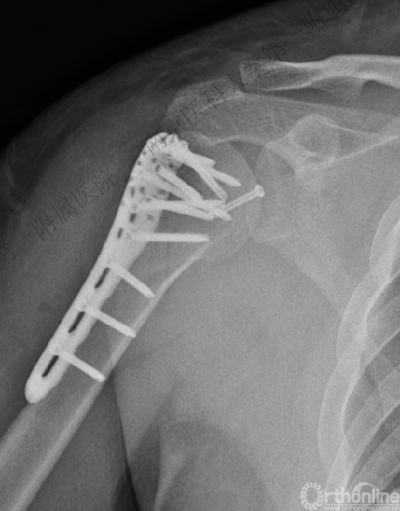

术后肩关节X线正位片